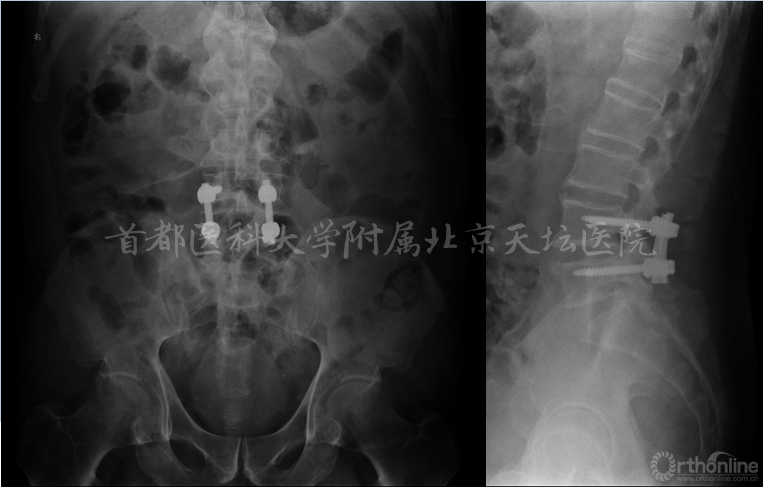

主诉:腰椎术后6年,腰痛1年,进行性加重伴双下肢麻木无力8个月

现病史:患者6年前出现腰痛伴右下肢放射痛,麻木及无力,于外院行棘突间内固定装置(Wallis)手术,术后症状部分缓解,未复查。1年前患者再次出现腰痛及下肢放射痛,8个月来呈进行性加重,现疼痛剧烈,不能久坐,不能站立及行走,平卧位不能缓解,服用止痛药物效果不佳。

影像资料:

诊断:

• 腰椎管狭窄症(双侧神经根管狭窄)

• 棘突间植入物术后(Wallis)

• 棘突骨折